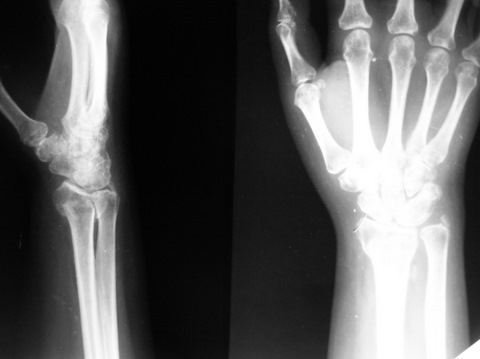

Обратилась женщина 45лет, профессия - швея, травма 24.02.07

вколоченный перелом правого луча (см Ргр Р******279). Лечилась:

На данный момент женщину беспокоят слабокупирующиеся боли

плечо-локоть-кисть по локтевой поверхности больше, ограничение

движений в л\з суставе и мелких суставах кисти (см приложения: общий

вид, объем движений  - рис. Р*******272, Р******271), на Ргр нарастают

явления остеопороза, не смотря на прием препаратов кальция(рис.

Р****277,278).